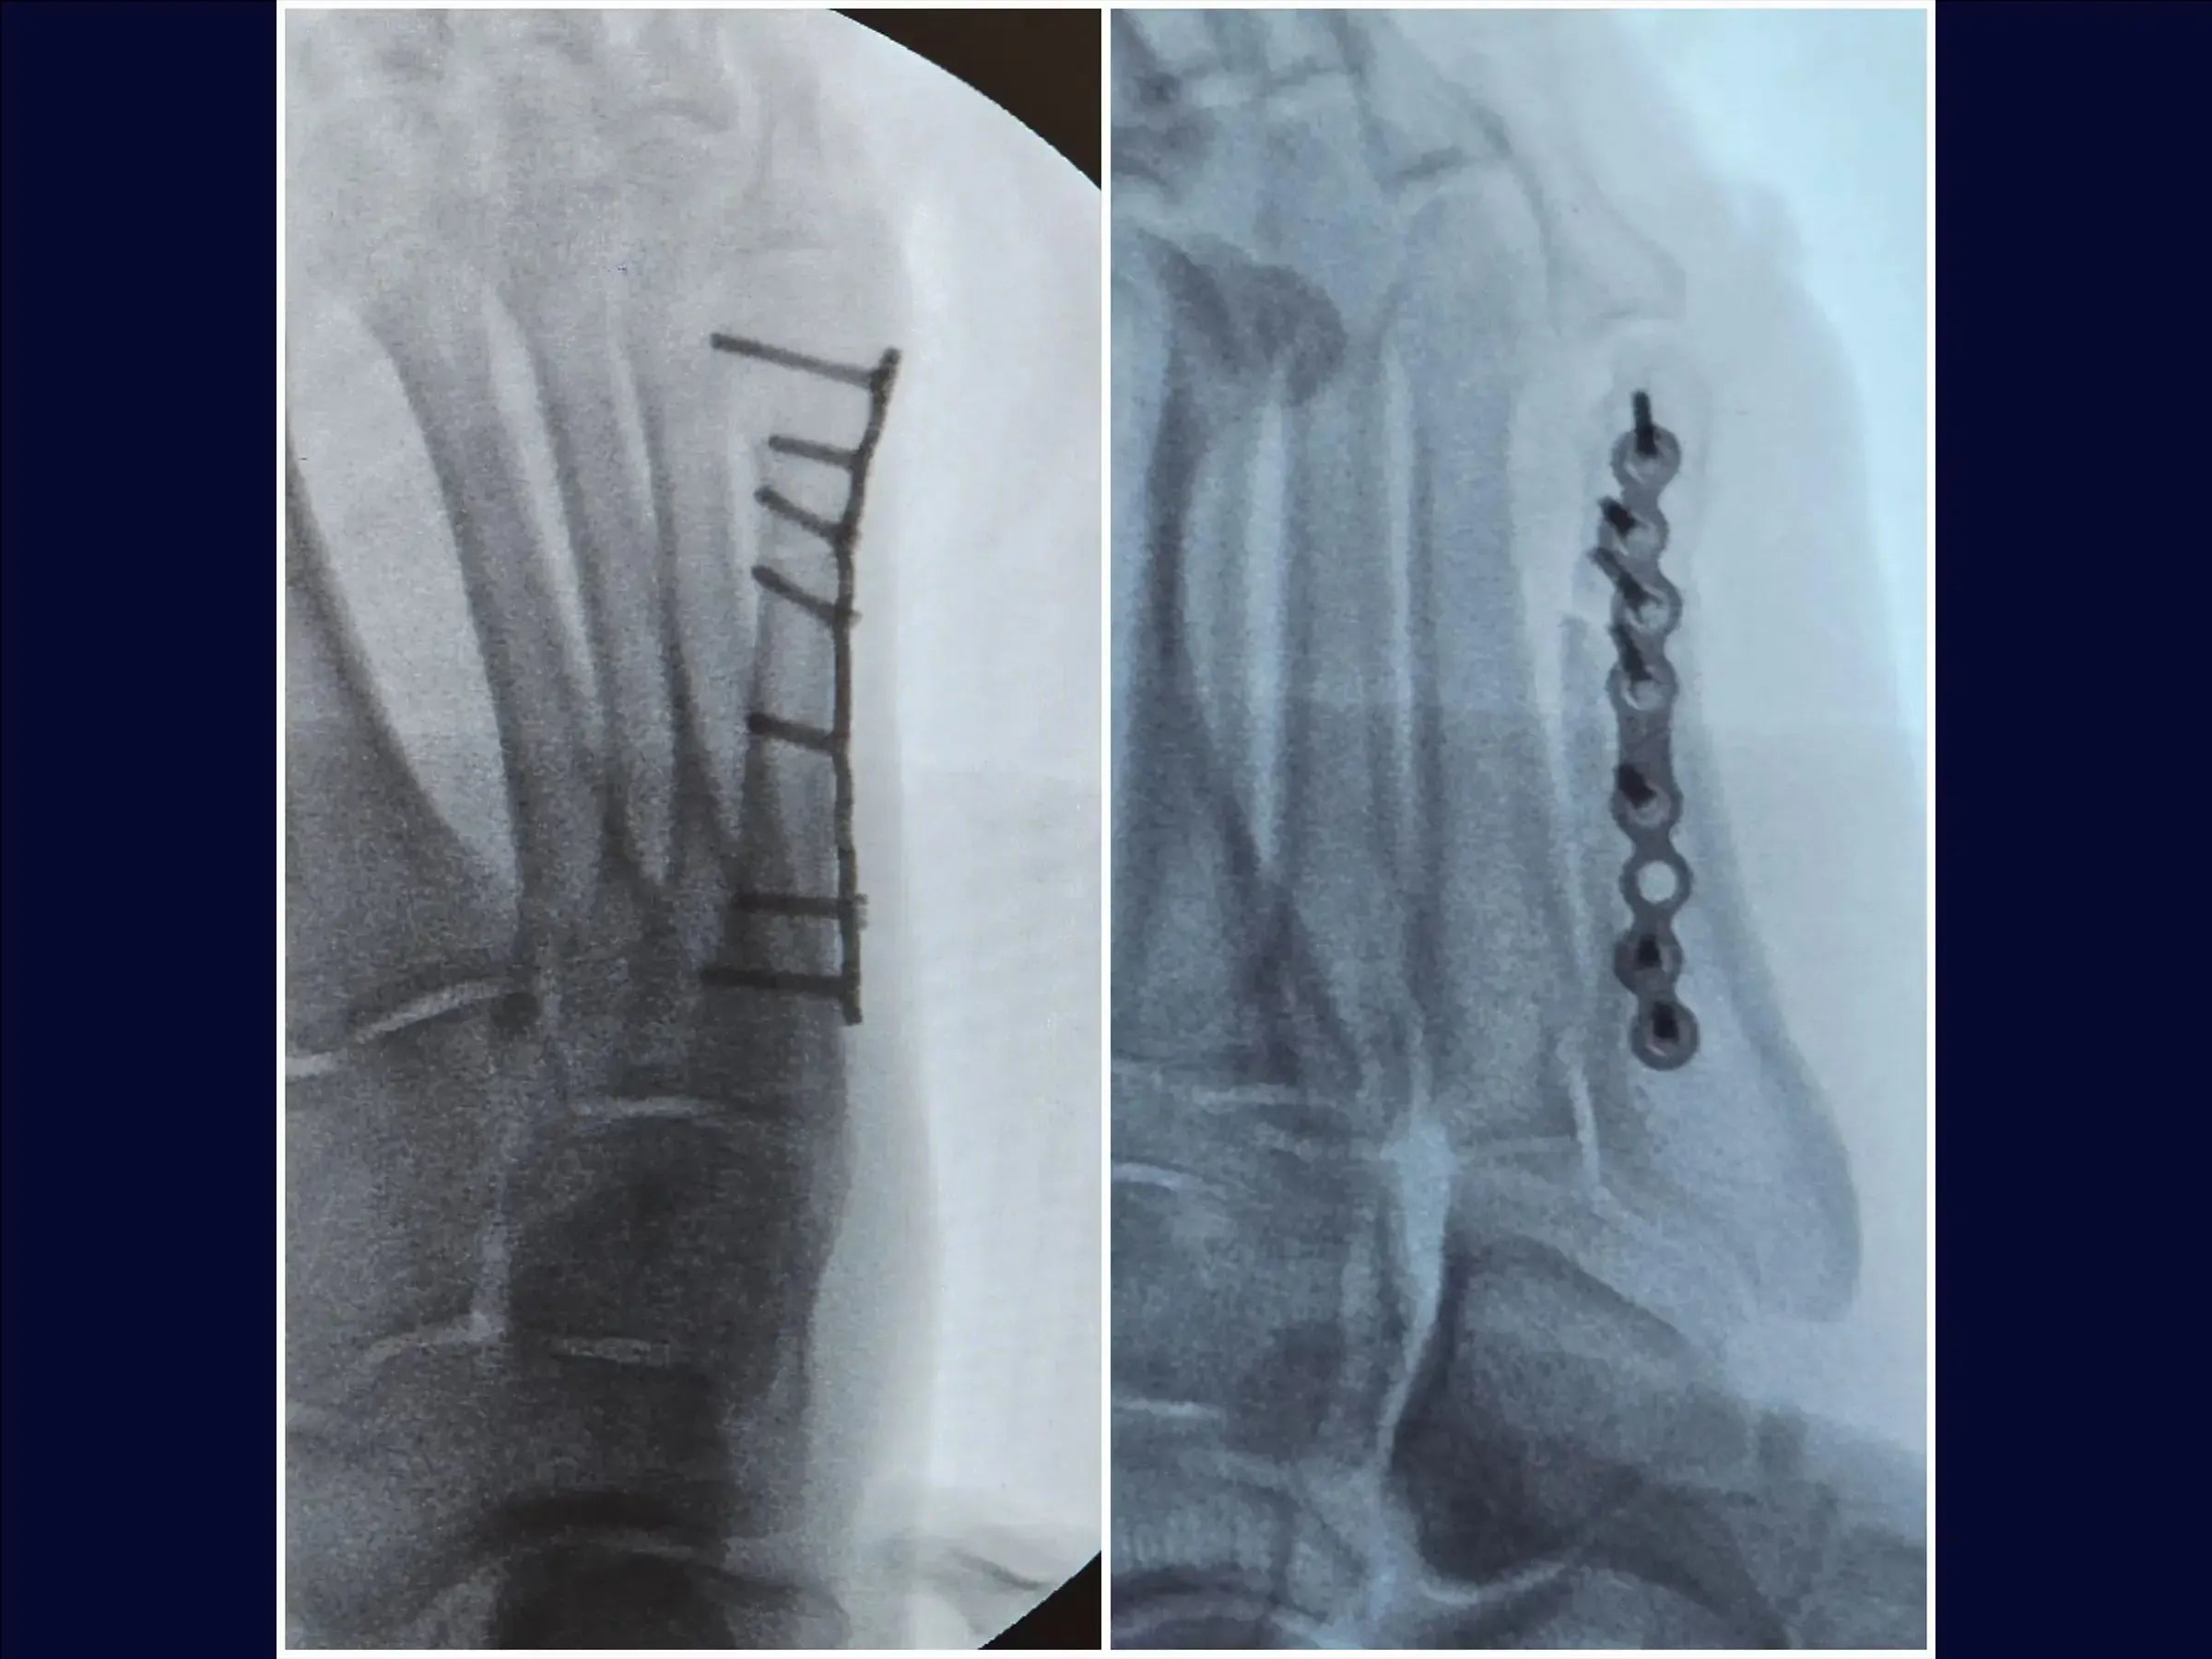

- Reducción de la fractura y estabilización provisional: Identificación de los vértices de la fractura, reducción bajo visualización directa con pinza de reducción y estabilización provisional con agujas de Kirschner, evitando la zona de la futura placa.

- Fijación Definitiva con Placa Bloqueada: Colocación de una placa minifragmentaria de perfil bajo, utilización de tornillos largos para una adecuada distribución de la carga y reducción de la necesidad de futuras extracciones.

- Cierre y resultados: Cierre plano, con demarcaciones para resultados estéticos. La fijación estable permite la carga temprana con calzado de suela rígida.